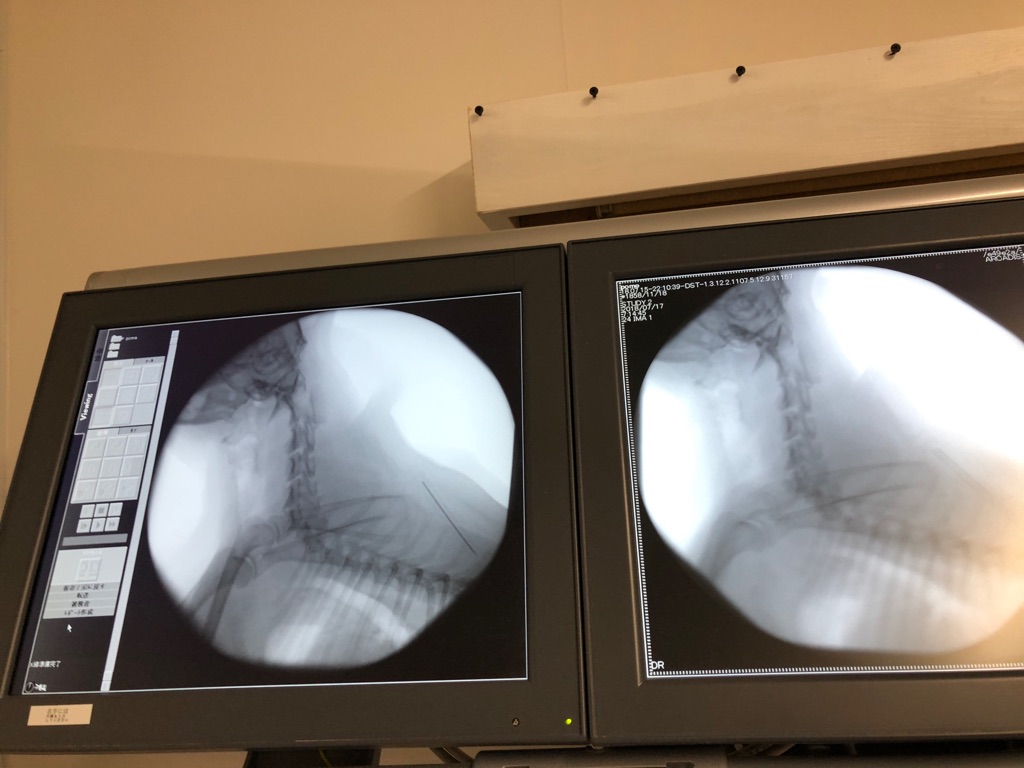

一昨日の夜に 気管虚脱の手術になり 今は

安静にしているジュンちゃんです、

症状は改善されて来ています 、1週間くらいすれば フリーで遊べるようになります。

あの苦しそうな息遣いも だいぶ無くなりました(*≧∀≦*)

本当に良かったです、先生が 神様に見えて来ます  (^◇^)